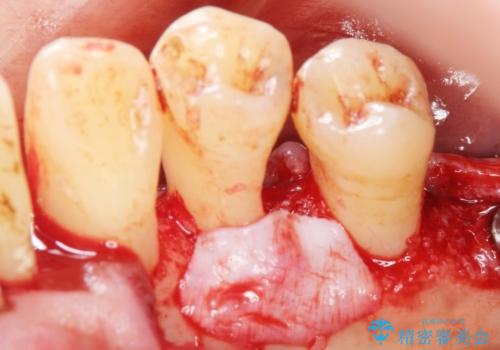

できるだけ自分の歯を残したいという患者様の強いご希望により、禁煙指導後再生療法(骨を増やす手術))を行いました。

再生療法から1年後リエントリー手術により骨の再生を確認し、骨外科処置(骨を平らにして歯周ポケットの根本的な改善を図る処置)を行ったのち、連結補綴を行いました。